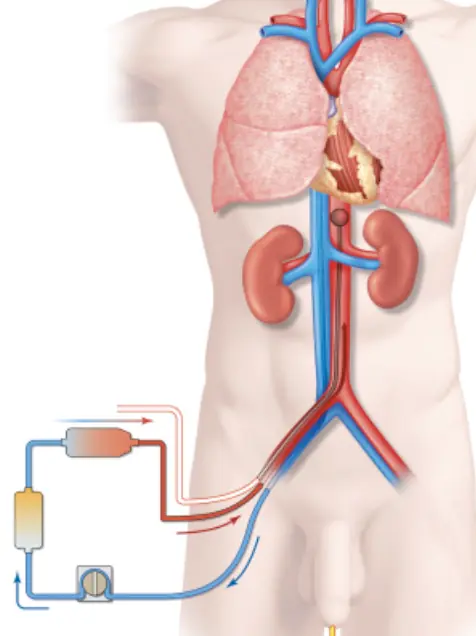

Protocole ECMO VV 2021

alexandre.noel le 12/09/2024